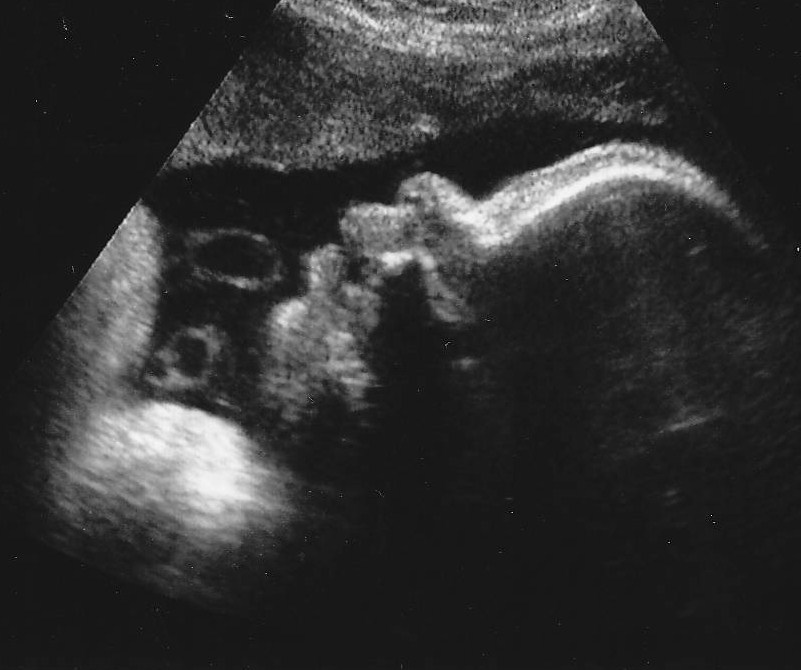

From pinterest.com

Triplets This is the only picture where they were seen alltogether Can A Baby Measure Bigger On An Ultrasound Toward the end of your third trimester, your health care provider or another member of your health care team might. You may measure perfectly for your due date, or larger or smaller,. If ultrasound exams during pregnancy show a baby is very large, your healthcare provider may recommend early delivery. A good example for these is the fundal height and. Can A Baby Measure Bigger On An Ultrasound.